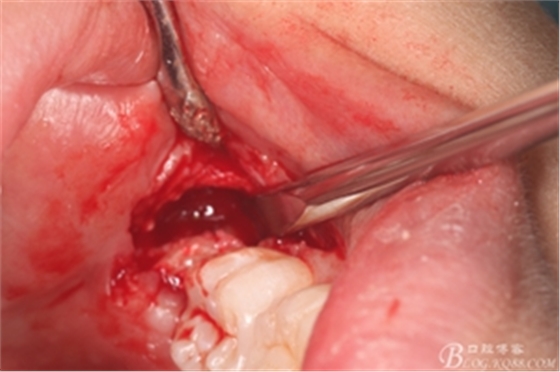

圖8. 翻瓣:建議翻小瓣

圖9.翻開瓣,可見38部分牙冠暴露

圖10. 翻開瓣。38牙冠還有部分骨質(zhì)覆蓋,遂用高速牙鉆去骨

圖11.去骨---暴露出38的牙冠最大周徑